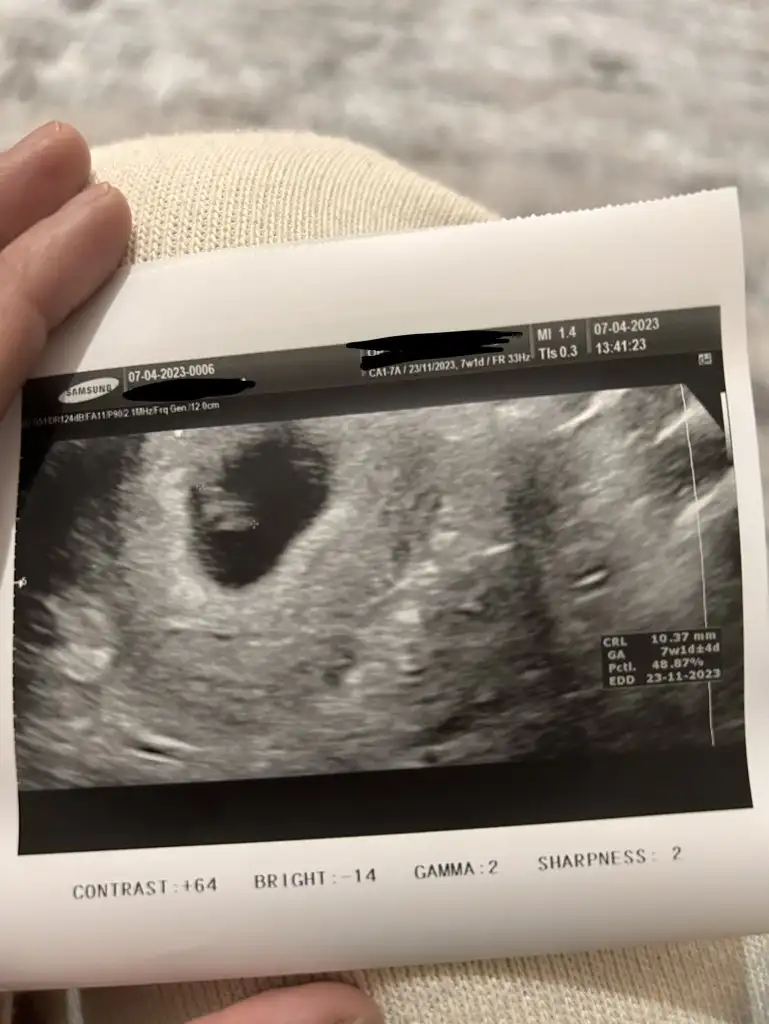

Merhaba arkadaşlar bizde 7+1'iz vajinal acaba yorumlayabilir misiniz? Teşekkür ederim.

,